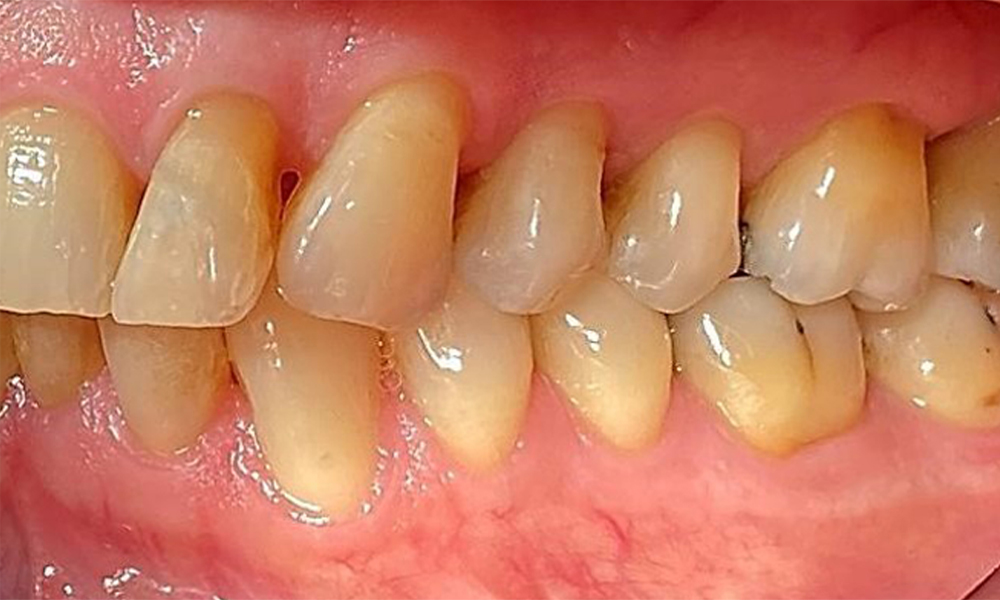

Изглед от лявата страна, включващ рецесиите.

Фиг. 4 Изглед от лявата страна, включващ рецесиите. © д-р Р. Крапф

Пациентът има пълно съзъбие с 28 зъба, което включва амалгамни и композитни пломби в областта на моларите и премоларите. На зъб 14 има видима клинична маргинална празнина. Зъб 27 има адекватна златна инкрустация. Налице са и генерализирани атриции и абразии. (фиг. 2, фиг. 3, фиг. 4, фиг. 5, фиг. 6)

Пациентът е с пародонтит II стадий, степен В (5). Клиничните дълбочини на сондиране от 1 до 3 mm са във физиологичния диапазон. Локализирани дълбочини на сондиране от 5 mm са наблюдавани медиопалатинално на 17 и 27. Налице са генерализирани рецесии от 1 до 3 mm с частична загуба на интердентални папили (фиг. 2, фиг. 3, фиг. 4)